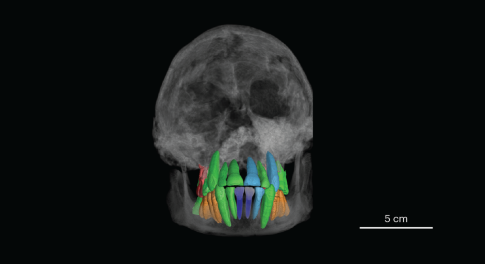

RNA-sequencing analysis of cells in the human cortex enabled identification of diverse cell types, revealing well-conserved architecture and homologous cell types as well as extensive differences when compared with datasets covering the analogous region of the mouse brain.